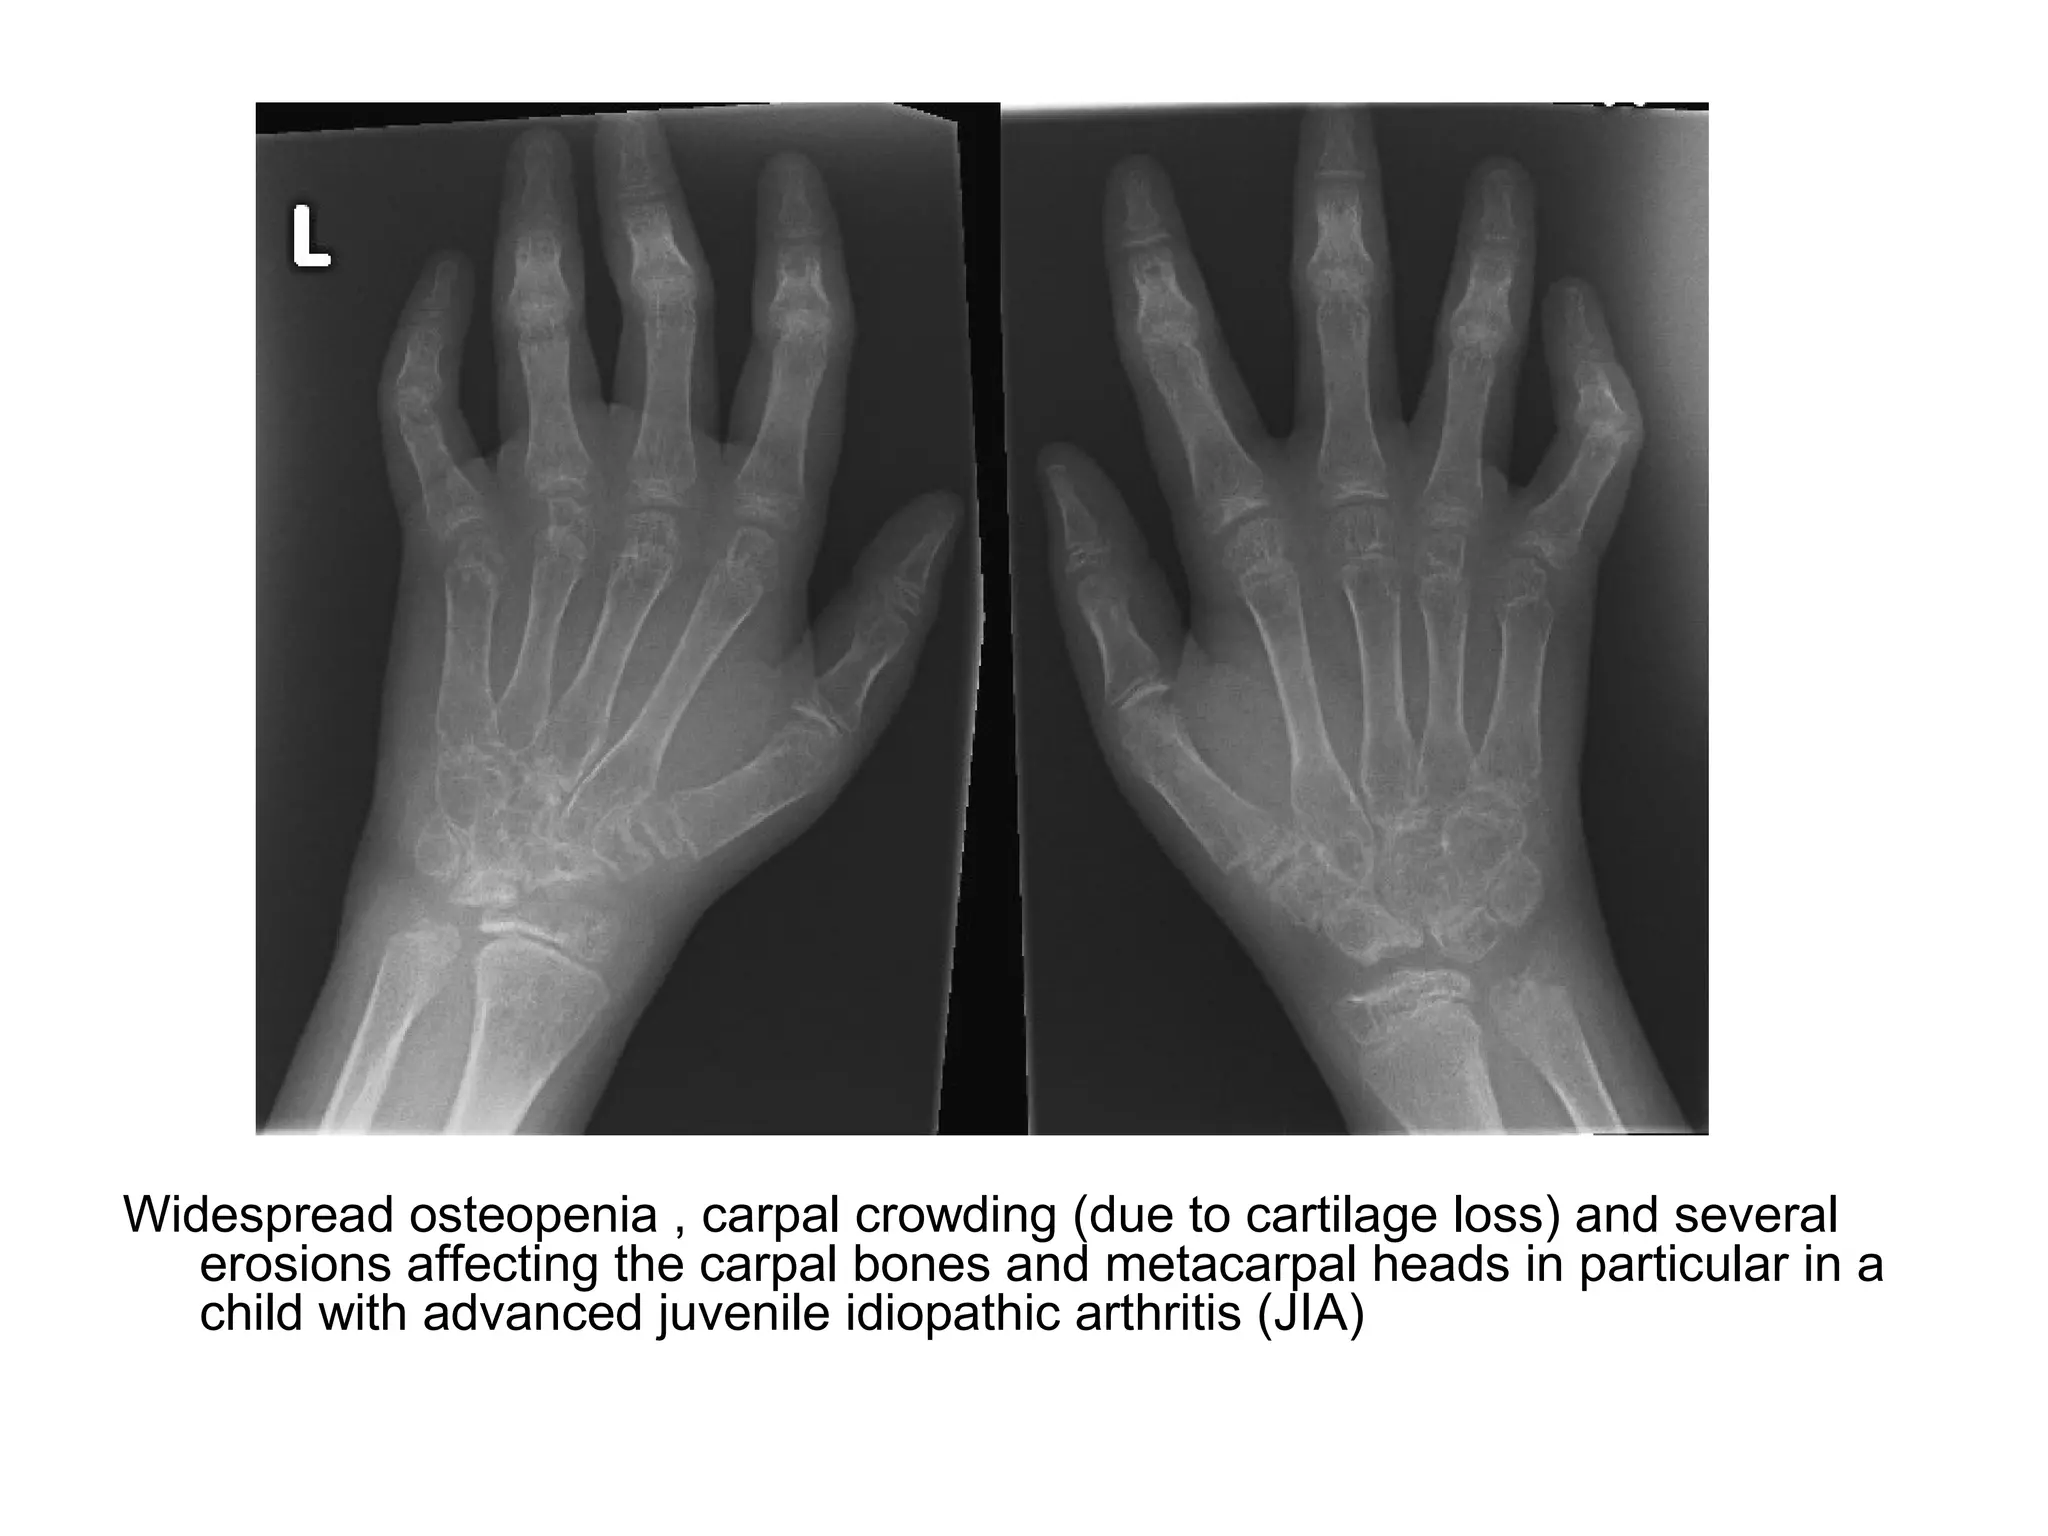

Widespread osteopenia , carpal crowding (due to cartilage loss) and several

erosions affecting the carpal bones and metacarpal heads in particular in a

child with advanced juvenile idiopathic arthritis (JIA)